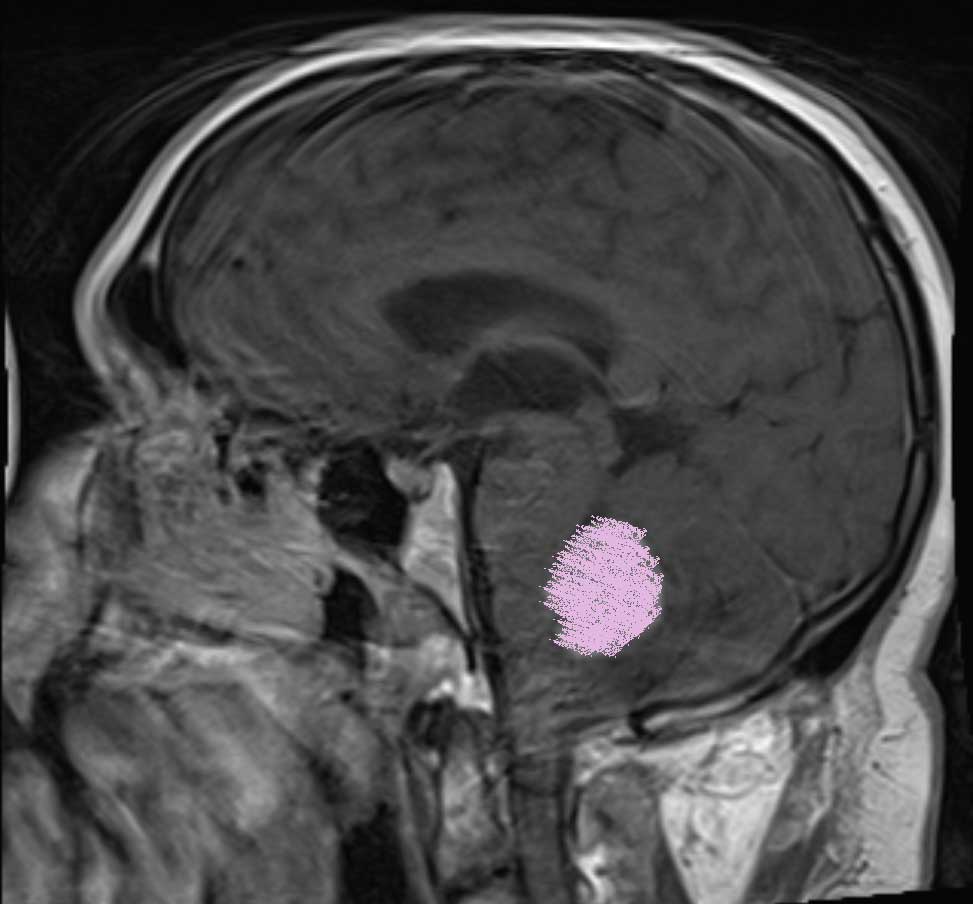

I was diagnosed with a Posterior Fossa tumor 10 days ago.

With that said, the tumor continues to press upon my brain stem and I am in bad shape.

(the lower image shows the Tumor pressing on the brain stem)

(the other white areas are cerebral fluid channels)